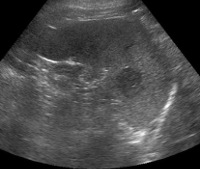

Во время ультразвука визуализируется структура паренхимы и оценивается размер и топография органа. Иногда назначают дополнительное УЗИ селезенки, по результатам которой можно оценить кровоснабжение подозрительных узлов, скорость кровотока в селезенке, артериях, венах.